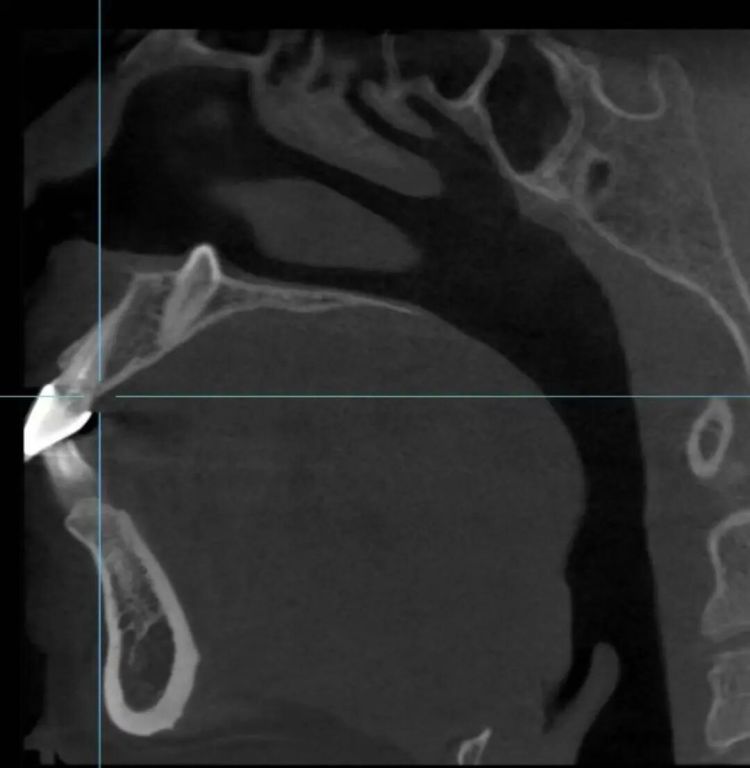

“这颗多生牙的牙冠向上,朝鼻腔方向伸长,牙尖已突破鼻底骨头,触及鼻底黏膜。如果不处理,在正畸移动牙齿的过程中,它会形成巨大阻碍,导致邻牙牙根吸收、正畸失败,甚至可能在未来穿破鼻腔,影响健康。”台州市康复医院口腔科主任医师戴杰介绍。

“其实,这是一种被称为‘埋伏多生牙’的情况。多生牙,顾名思义,就是正常牙列数目之外长出来的牙齿,可能出现在颌骨的任何部位,最常见于上颌前牙区。”戴杰解释道,发育过程中,该患者多生牙的牙胚不像正常牙齿一样向下萌出,而是“迷了路”,朝相反方向——即鼻腔底部生长,“由于上颌骨前牙区上方紧邻鼻腔,这才形成了逼近鼻腔的特殊位置。”